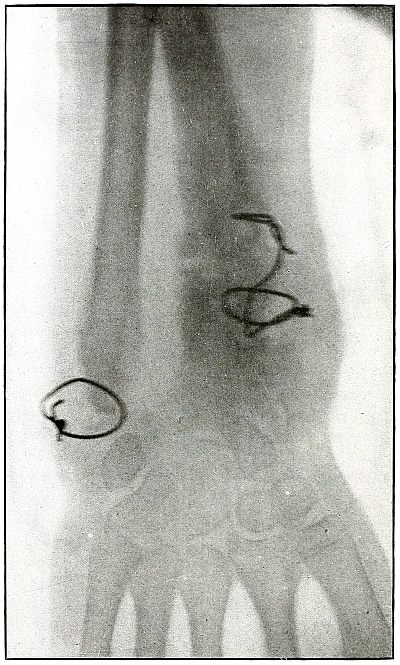

72. Gunshot fracture, ankle 154

73. Gunshot wound, heel 156

74. Gunshot wound, heel 158